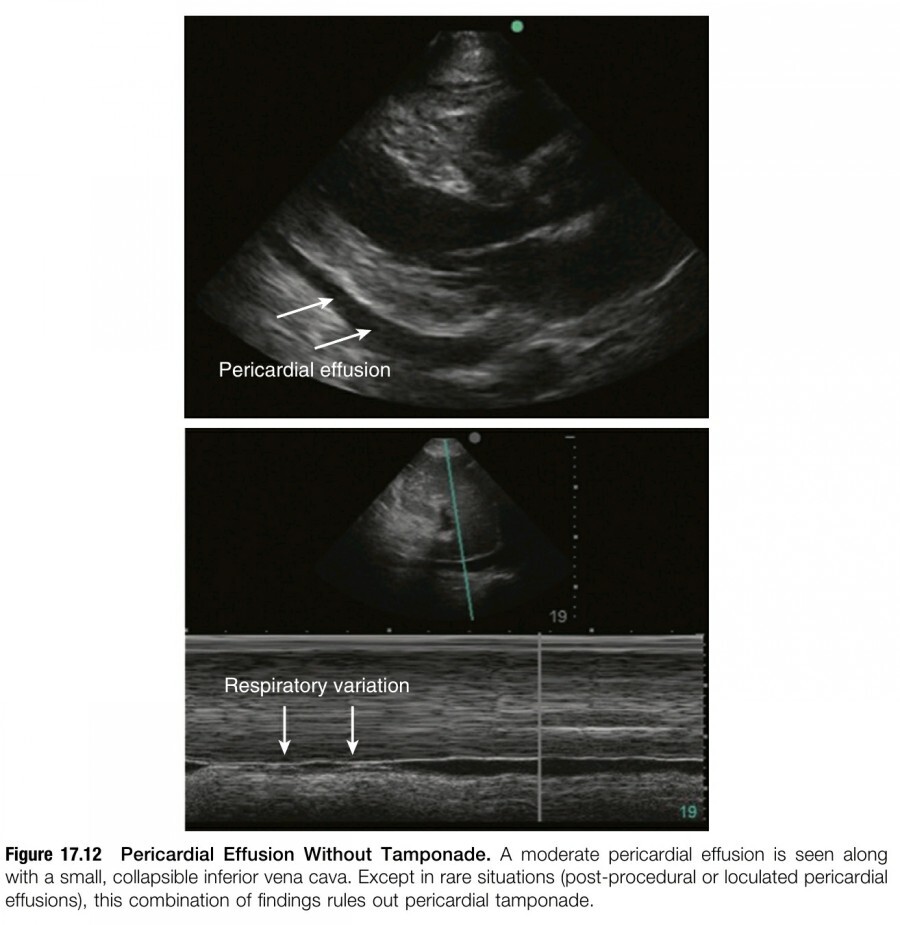

Pericardial effusion이 확인되고 cardiac tamponade가 의심된다면, IVC ultrasound는 pericardiac sac 안의 pressure가 right atrial pressure와 CVP를 상회하는지 여부를 확인할 수 있는 sensitive screening tool이다. Pericardial effusion이 있고 plethoric IVC(deep inspiration 후 50% 미만의 collapse가 있을 때)를 보이는 경우 tamponade 진단에서 sensitivity는 97%이지만, specificity는 단 40%이다. 따라서 tamponade가 의심되는 경우, deep inspiration 시 IVC collapse가 50% 이상이라면 더 이상의 추가적인 echocardiographic technique 없이도 tamponade를 효과적으로 rule out 할 수 있다(figure 17.12).